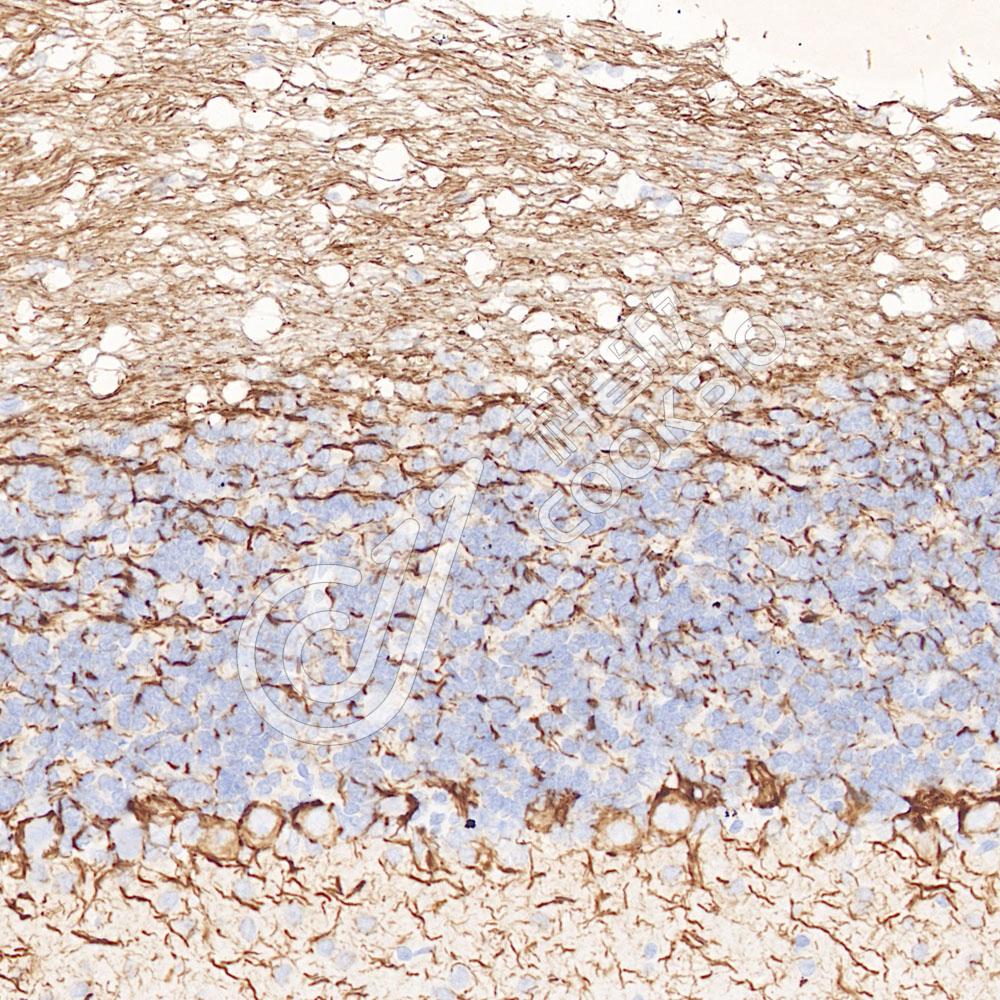

IHC检测160 kDa Neurofilament Medium蛋白(货号 K547289).

样品: 猴脑, 4%多聚甲醛 (货号KSG1101) 固定12-24小时.

抗原修复: Tris-EDTA抗原修复液(pH 9.0) (KSG1203), 98℃, 20分钟.

—抗: 1: 800稀释, 4℃ 孵育过夜.

二抗: S-vision免疫组化多聚二抗(山羊抗小鼠), 即用型(货号KB3903), 室温孵育20分钟.